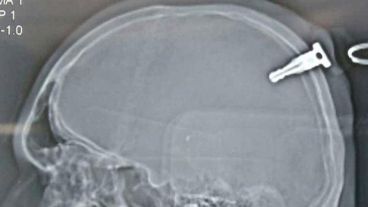

Un joven hindú de 19 años fue golpeado con una llave en la cabeza y la misma le perforó el cerebro unas 1,5 pulgadas (3,8 centímetros). El hombre tuvo que someterse a una cirugía de 3,5 horas para extraer la llave y afortunadamente sobrevivió.

“Por suerte no sufrió hemorragia interna y no hubo daño cerebral”, dijo Ashish Bhandari, administrador del Hospital Anand Rishi, donde el paciente fue tratado. “Si se hubiera producido una hemorragia interna severa, podría haberle costado la vida”, agregó.